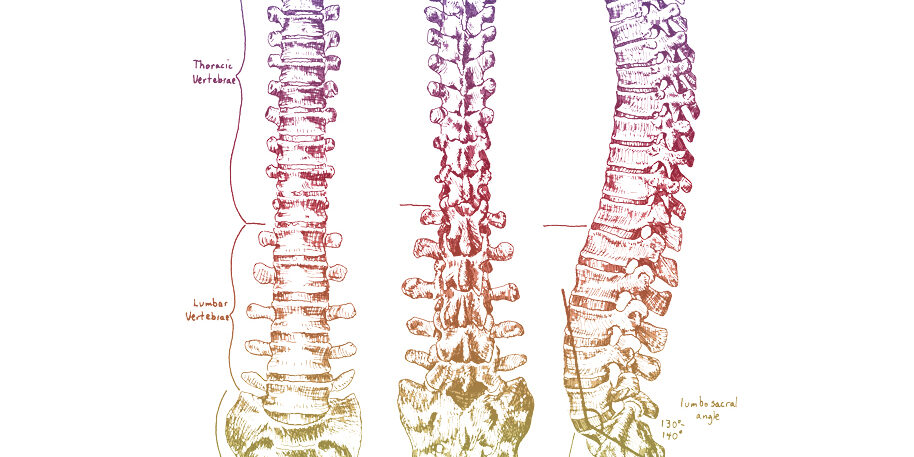

The same reason a bulging or herniated disc can put pressure on a nerve and cause pain is the same reason a subluxation, or dysfunction within the spinal joints, can create the same kind of pressure and interference with the nerves and nervous system. Restoring proper function to these joints and ensuring that your nervous system is free of interference through chiropractic care can help you feel great. Many patients of ours also report improvements like: